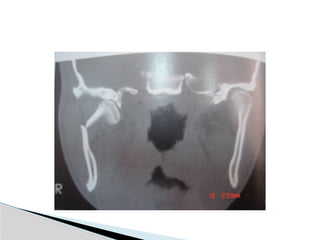

CT

Significant displacement or dislocation,

mechanical obstruction, mult trauma pt, &

intracapsular fracture.

Conventional Radiology At least2 views at right angle to each other. Mandibular series: PA, Lateral oblique or panoramic, & Towne’s view (projects condyle below mastoid process). CT Significant displacement or dislocation, mechanical obstruction, mult trauma pt, & intracapsular fracture. MRI St injuries: effusion, visualization of disc. Imaging